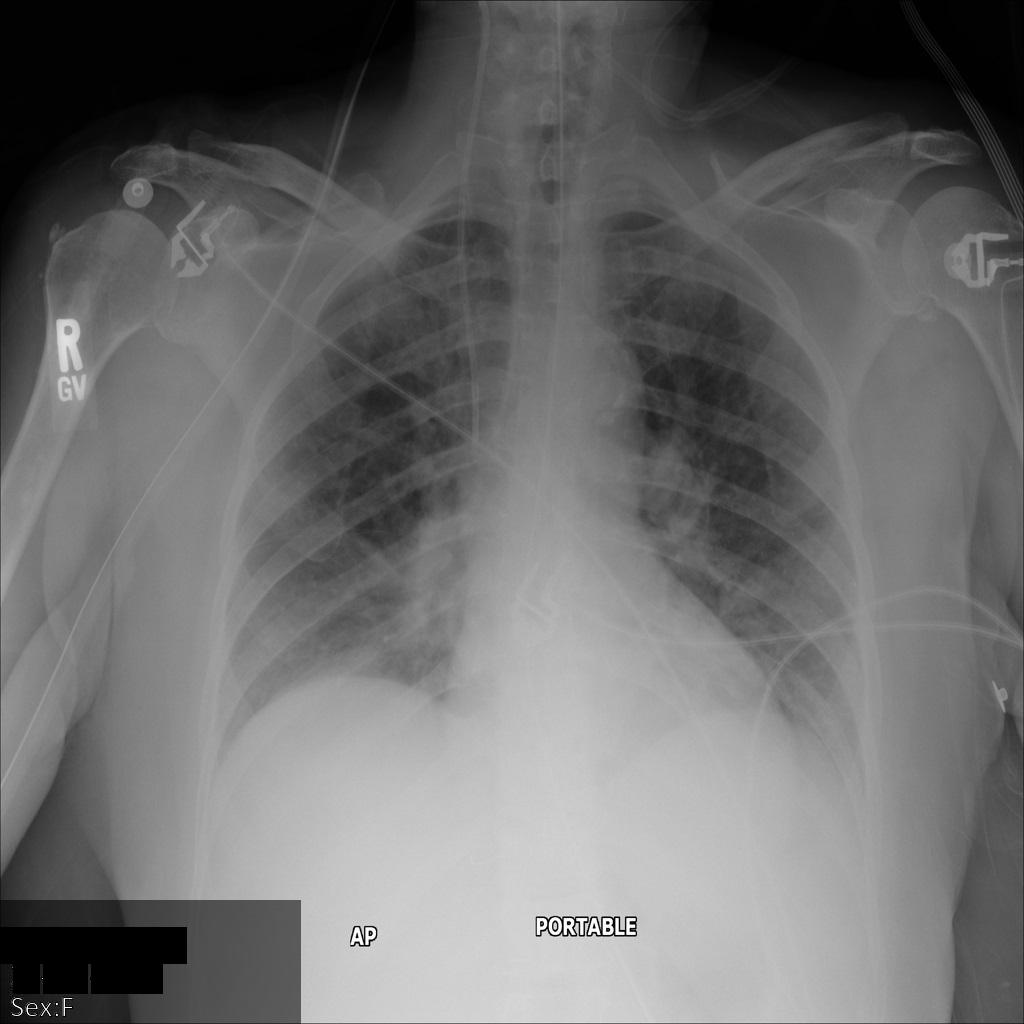

使用 REDACT_SENSITIVE_TEXT 选项将图片提交到 Cloud Healthcare API 后,图片显示如下:

您可以看到以下情况:

- 图片左下方的

PERSON_NAME已被遮盖 - 图片左下方的

DATE已被遮盖

根据默认 DICOM infoType,该患者的性别不属于敏感文本,因此未遮盖。